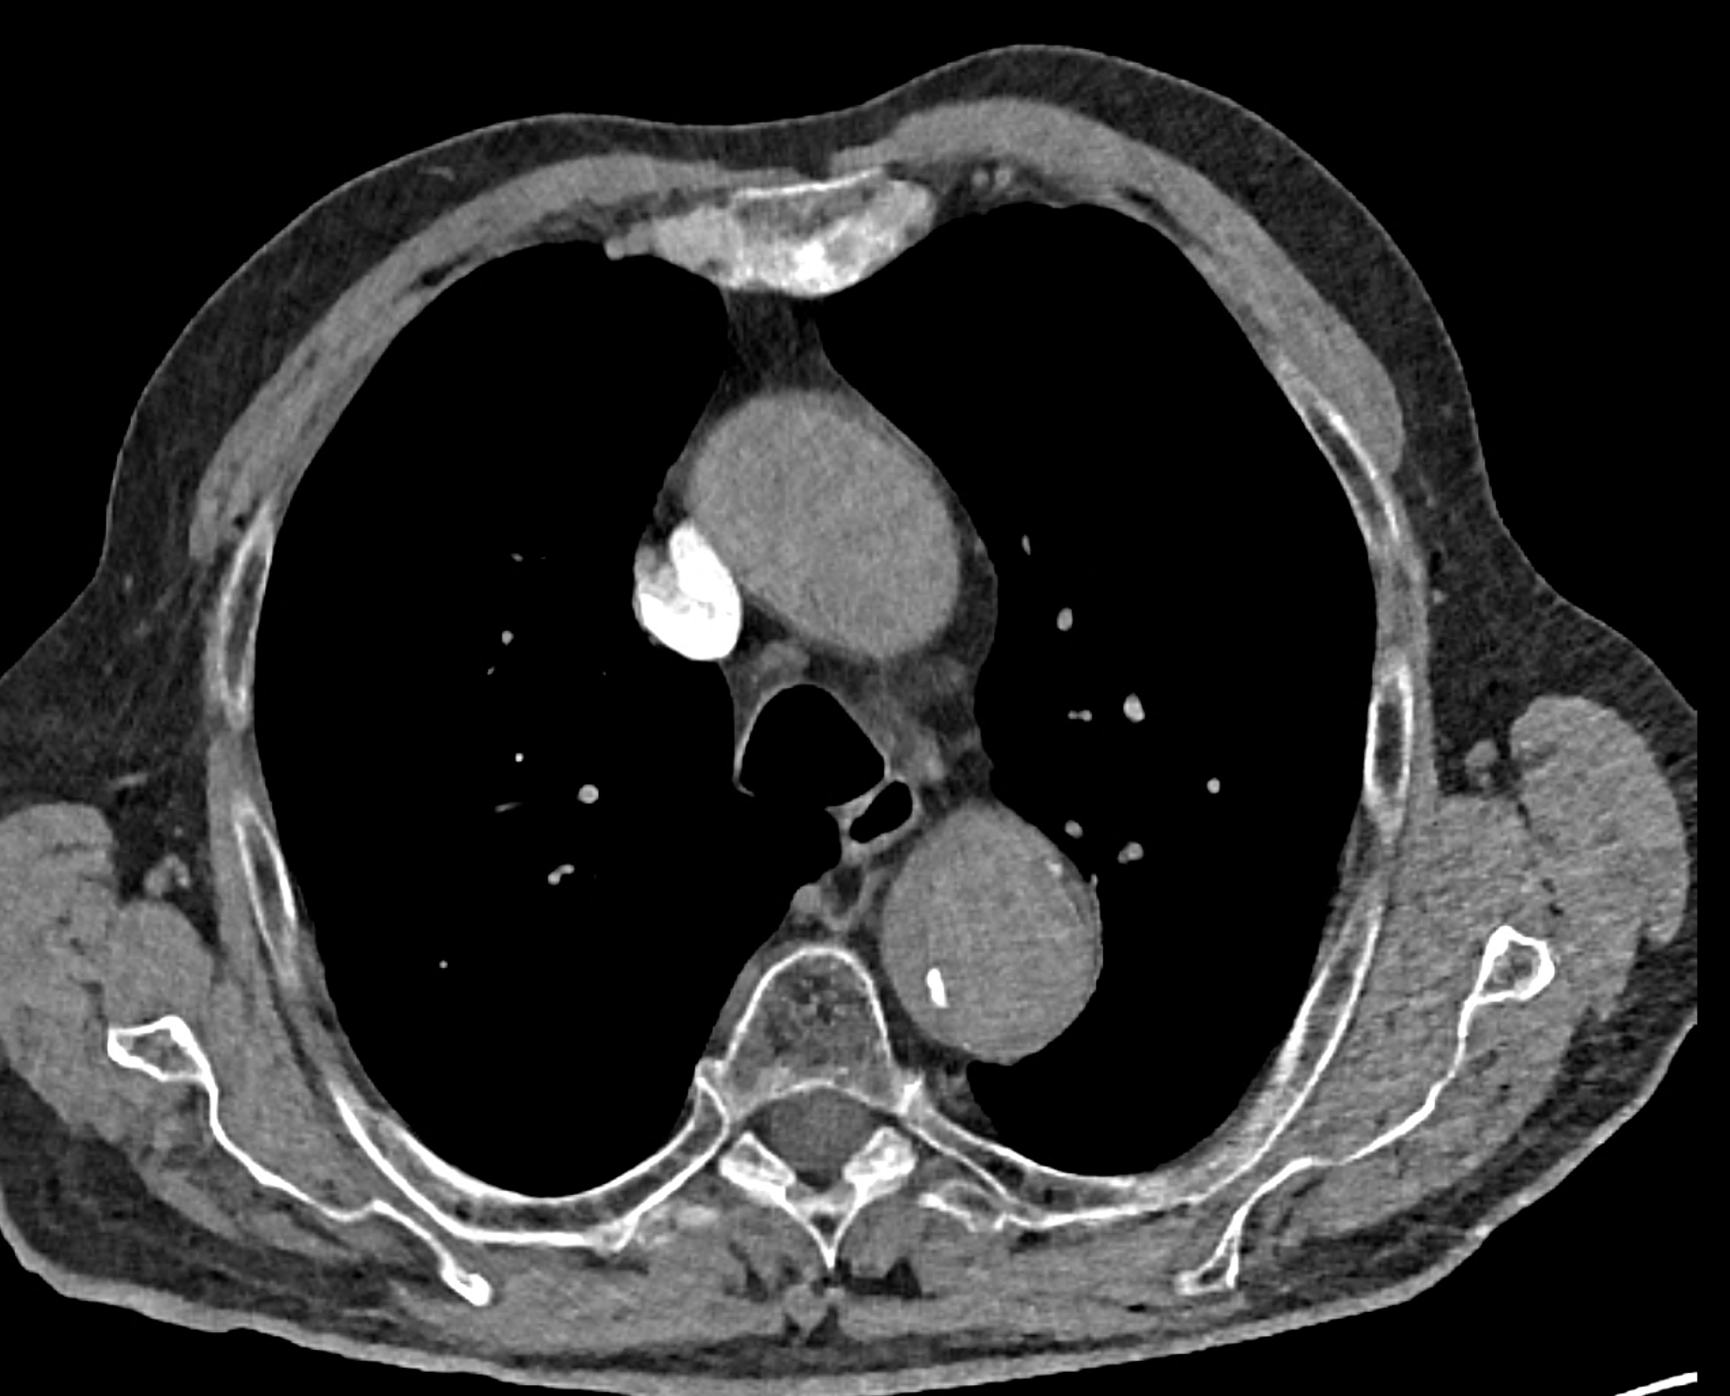

in patient chest pain, negative ECG but with elevated D-dimers was performed CTA of the chest to exclude highly suspected pulmonary embolism. No pulmonary embolism was see, but the pathology of the aortic arch and descending thoracic atorta. The images were consistent with aortic intramural hematoma type B according to the Stanford classification with incipient transformation in dissection – behind the subclavian artery, it is clear that the contrast agent is flowing into the intramural hematoma. Differentiation from wall thrombosis is facilitated by the presence of calcification in the detached intima, which is most clearly visible on virtual non-contrast imaging. The intramural hematoma itself exhibits different properties in terms of X-ray absorption. Coagulated blood is visible at the apex of the aortic arch, where it closely adjoins the area that is perfused and filled with contrast medium. There are other smaller areas filled with contrast medium at the sites of the intercostal arteries. These areas are secondary sites where the original intramural hematoma is channeled during its transformation into a classic aortic dissection.

Virtual non-contrast images help to distinguish between the intima and thus in the differential diagnosis of intramural hematoma versus wall thrombosis. Signs of fresh coagulated blood in IMH indicate bleeding into the aortic wall from the vasa vasorum. In contrast, monoenergetic images with lower energies of 40-55 keV highlight areas of intramural hematoma with active blood flow.

comparison of the the images 60, keV monoenergetic, virtual non-contrast (VNC), and iodine map images. The repercussion starts in the proximal tear of the intimate (the first three images), calcification in the intimate (next three images), tera at the level of the arising intercostal artery (last three images)

comparison of the sagittal aortic MPR in 40, 60, 140 and 190 keV monoenergetic images

comparison of the perpendicular planes to sagittal aortic MPR in 40, 60, 140 and 190 keV monoenergetic images